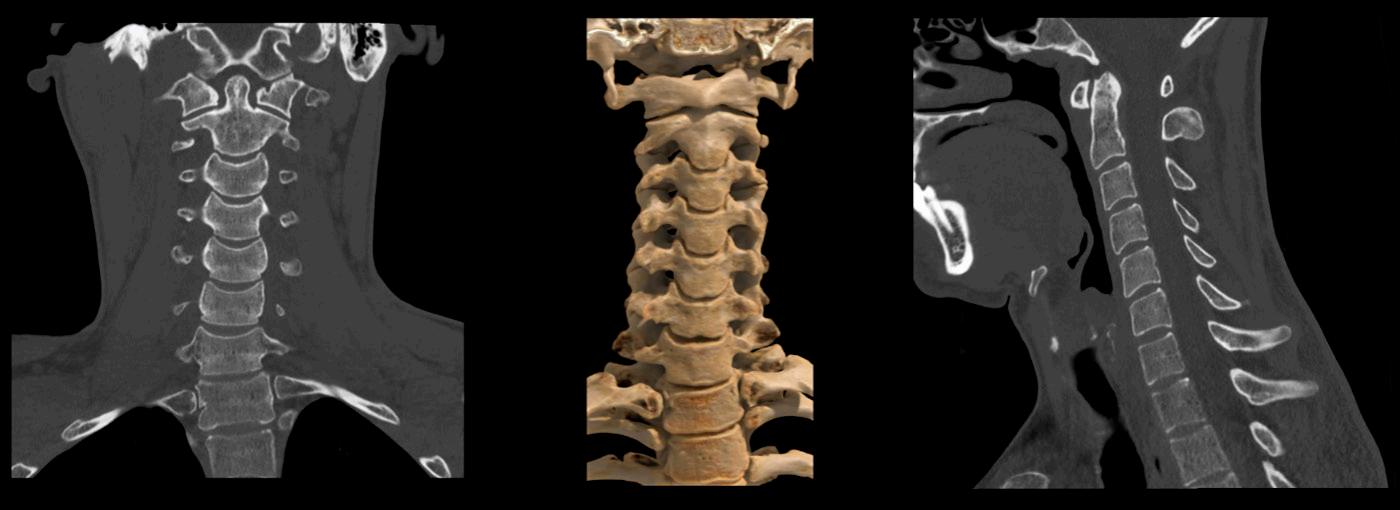

SilverBeam scan of the cervical spine. Images are showing reduced artefacts in the shoulder region.

Dr. Bull and his team also use the SilverBeam Filter for high-quality images at very low dose. SilverBeam is a filter for Aquilion CT that incorporates silver to selectively optimise the beam energy. It removes low-energy photons from the beam spectrum, which do not contribute to image quality, but do increase dose and scatter. When combined with Canon Medical’s

Advanced intelligent Clear IQ Engine (AiCE) technology, this beam-shaping energy filter can harness the power of AI to deliver high image quality and low noise for dedicated applications.

Dr. Bull commented, “We are not just going for low dose - we aim for high image quality at low dose. We are able to do that with SilverBeam. We don’t just use it for lung cancer screening, we use it for standard chest imaging. We also use it for bone imaging because we get much fewer artefacts and the dose is so much lower. If it’s a spine or if we are looking for a hip fracture, we will use SilverBeam.”